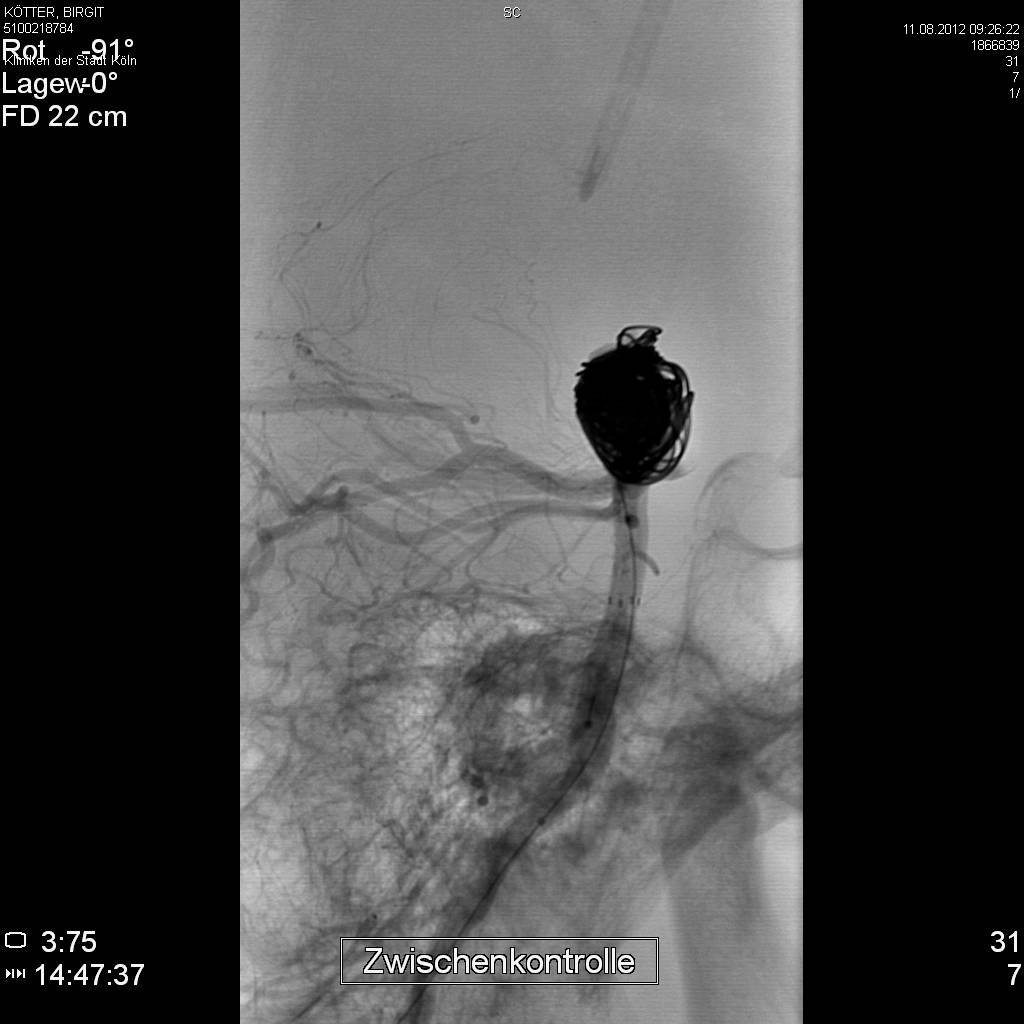

Am 11.08.2012 wurde das Aneurysma mittels des Coiling-Verfahren verfüllt:

image10